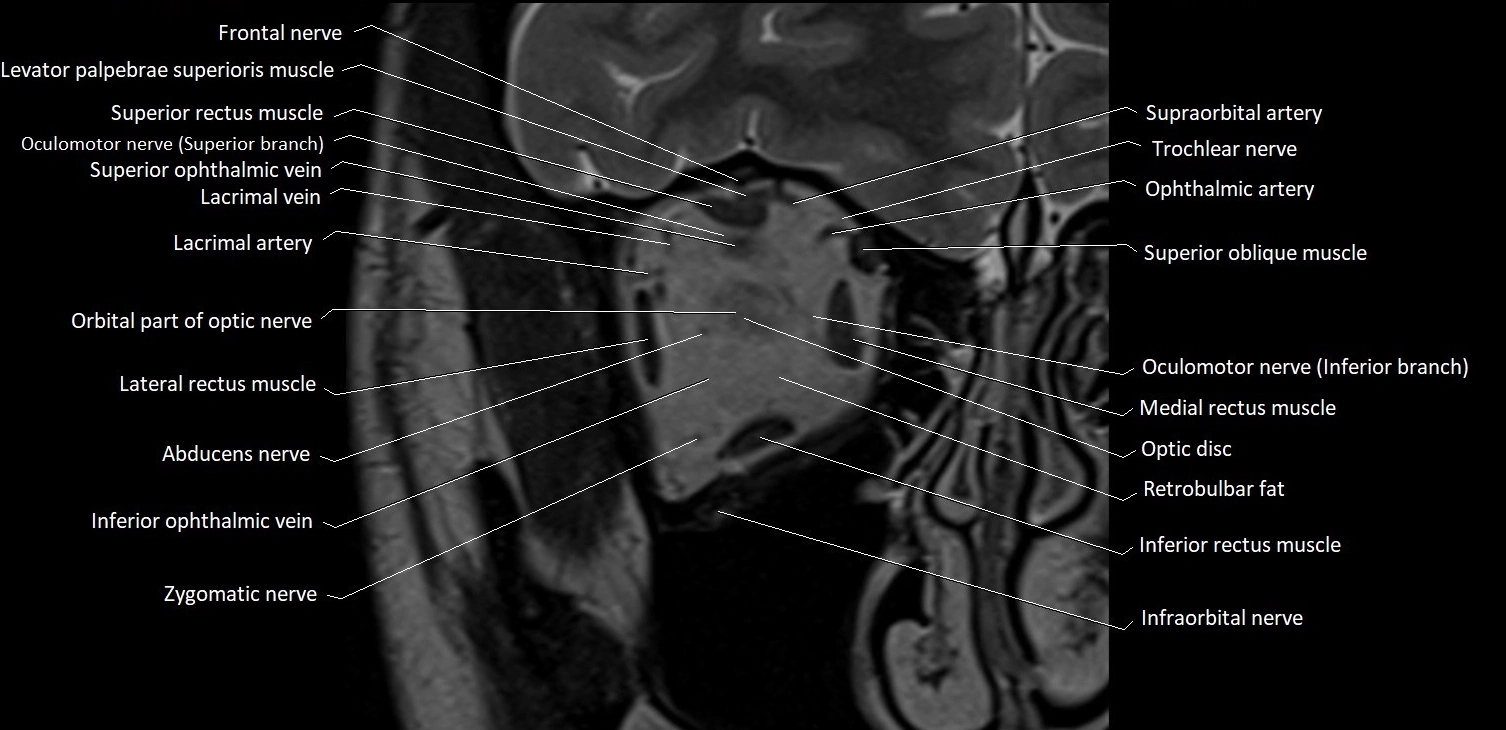

MRI images